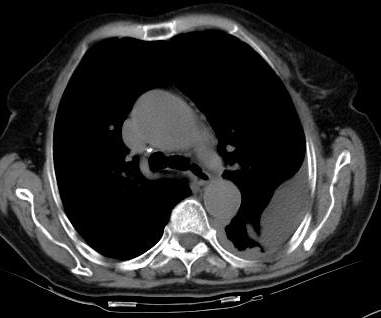

请上传纵隔窗。目前还是支技包裹性积液(明显梭形),即使是间皮瘤并积液也少梭形的。

标题: 回复:病历讨论,胸膜间皮瘤?(是同一个病人吧)

从图片看,包裹性积液好象更合理,梭形,ct值3-5hu(在哪看到的?);胸膜间皮瘤如此规则,不多见。

左侧背部胸膜肥厚,伴包裹性积液,不考虑间皮瘤.

同意以上各位的高见,首先考虑包裹性积液,1.胸膜间皮瘤积液量一般较大,以游离性积液更为常见,2.可以看到增厚的胸膜结节